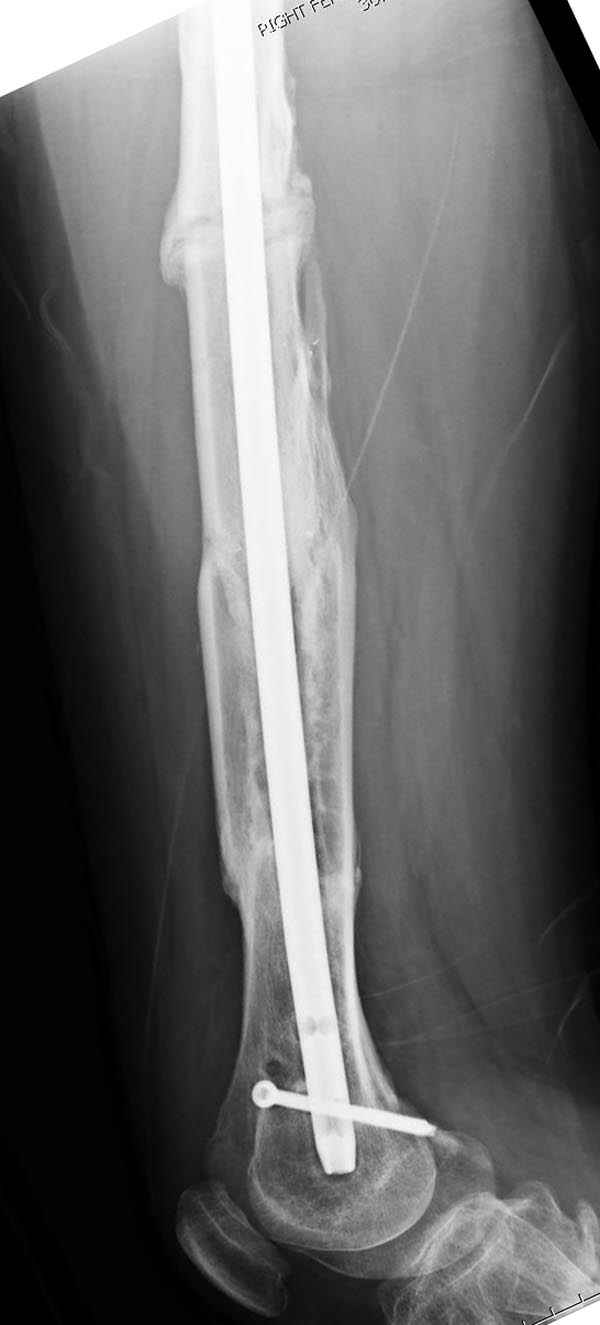

Замена реконструктивного штифта “Custom made Nail” с антибиотиком (рис №5, №6),

после промывки канала с рассверливанием внутреннего кортекса, через 4 недели антибиотический штифт удалили, оспалителный процесс остановлен и бедро сросся.

Мы не дождались “Happy End”, у больного IQ в пределах 70%, через 6 месяцев вернулся после небольшой травмы, споткнувшись получил перелом

того же бедра (рис №7).